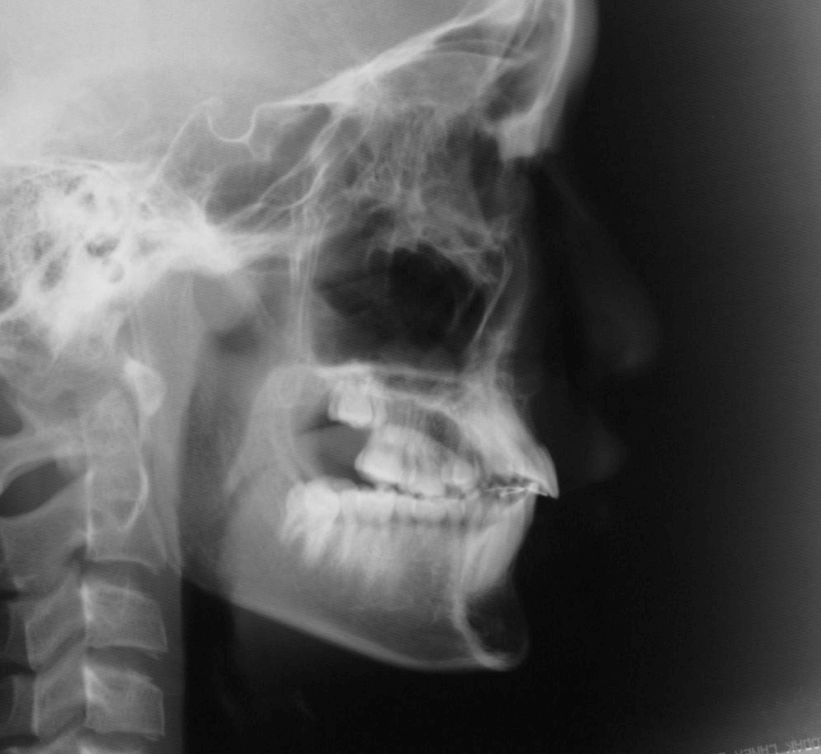

| 年齢・性別 | 11歳1ヶ月の女性 |

|---|---|

| 主訴 | 口元の突出感と歯並びが気になり、将来的な咬合状態を整える目的で来院された患者様です。 |

| 治療期間・回数 | 2年6ヶ月・25回 |

| 費用 | 720,000円 |